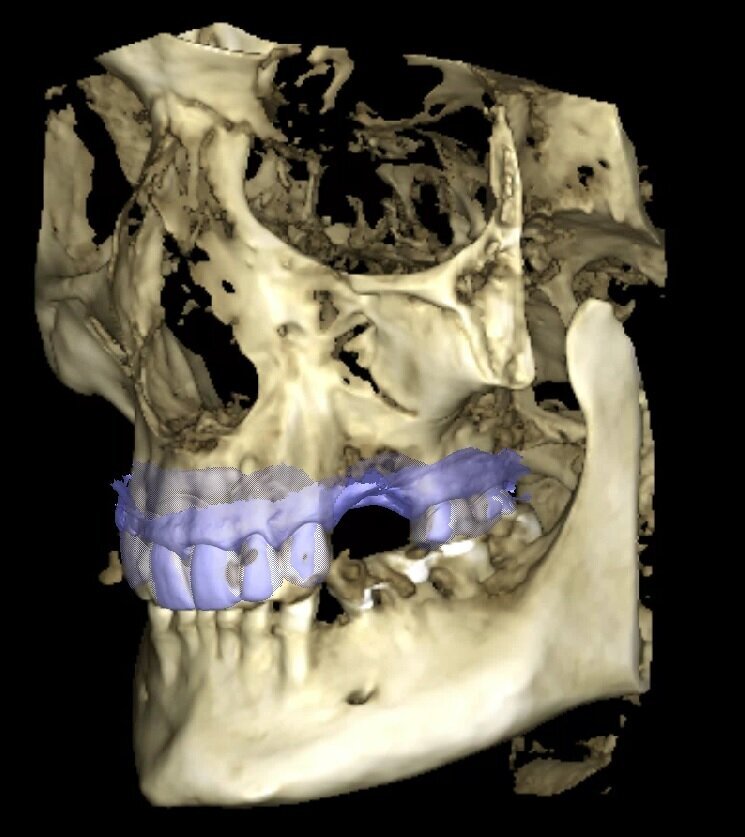

Rilevare 2 scansioni intraorali del paziente e sovrapporle ai dati della CBCT al fine di conoscere la posizione dei tessuti molli nello spazio, dato non sempre visibile nella CBCT causa interposizione della guancia o della lingua durante l’acquisizione dell’esame stesso (Fig. 3).

Fig. 3_Volume rendering con sovrapposizione dell’impronta intraorale in formato STL.